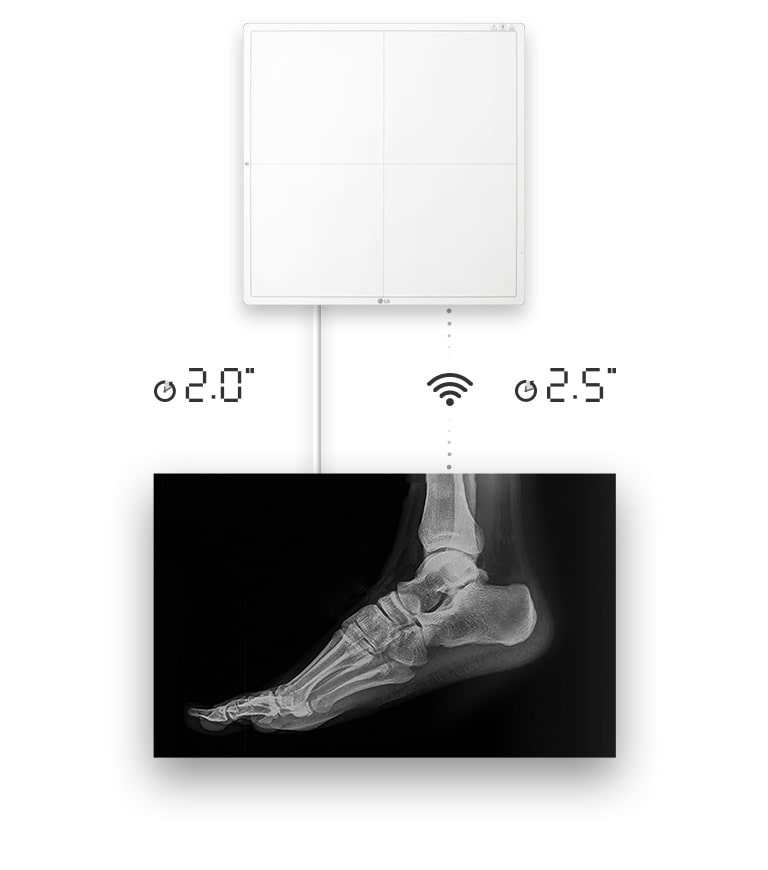

Rapid Image Availability

Image availability in 2 seconds with a wired connection, or 2.5 seconds with a wireless connection to get a raw image

- Raw Image in 2.5sec.(wireless)

- Raw Image in 2sec.(wired)